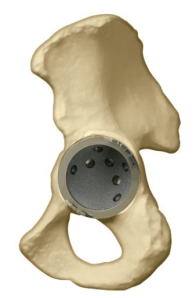

BHR Metal on Metal Acetabular Cup and Resurfacing Head - from http://www.rediscoveryourgo.com/Product.aspx?Product=BirminghamHip

BHR Acetabular Cup Sizing - from http://dl.dropbox.com/u/29303475/Cobalt/BHR_FDA_Surgical_Technique_NEW_06-07.pdf